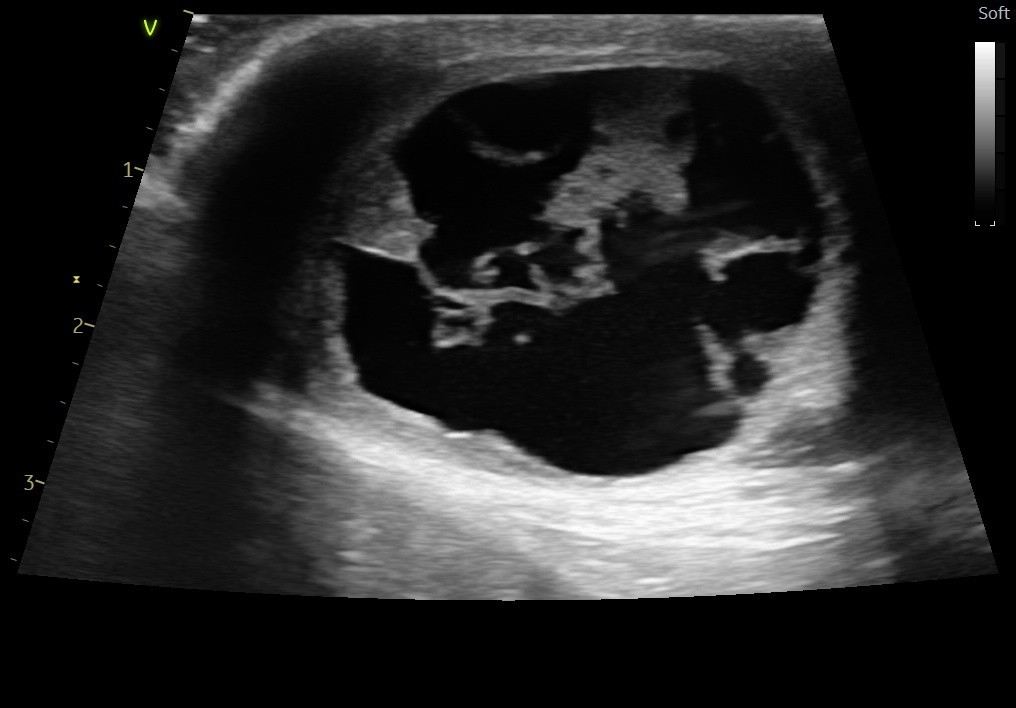

主诉最近发现两只睾丸的大小相差较大,精神状态尚可,挑食。于近日入院进行病变部位的超声检查,结果如图:

该图为肿大的左侧睾丸